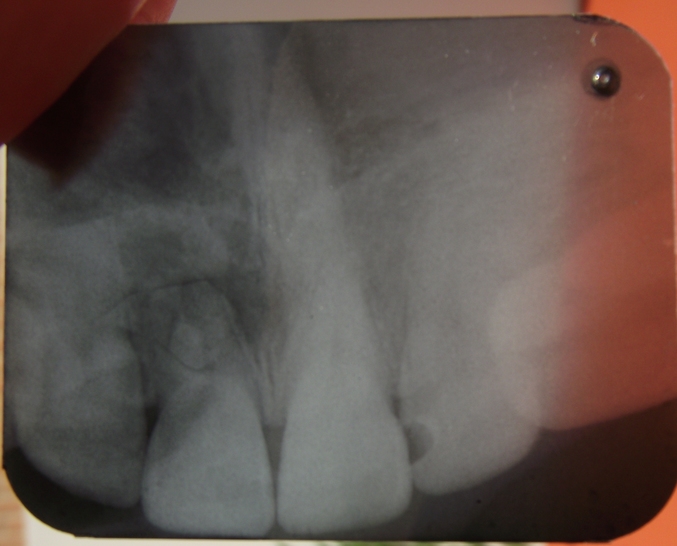

Здравствуйте!Вот отсканировала.Первый снимок,который побольше,был сделан через 5 дней после удара.Второй-через 35 дней. Зуб, получается, центральный левый,тот который через один от зуба с кариесом. Спасибо за внимание!